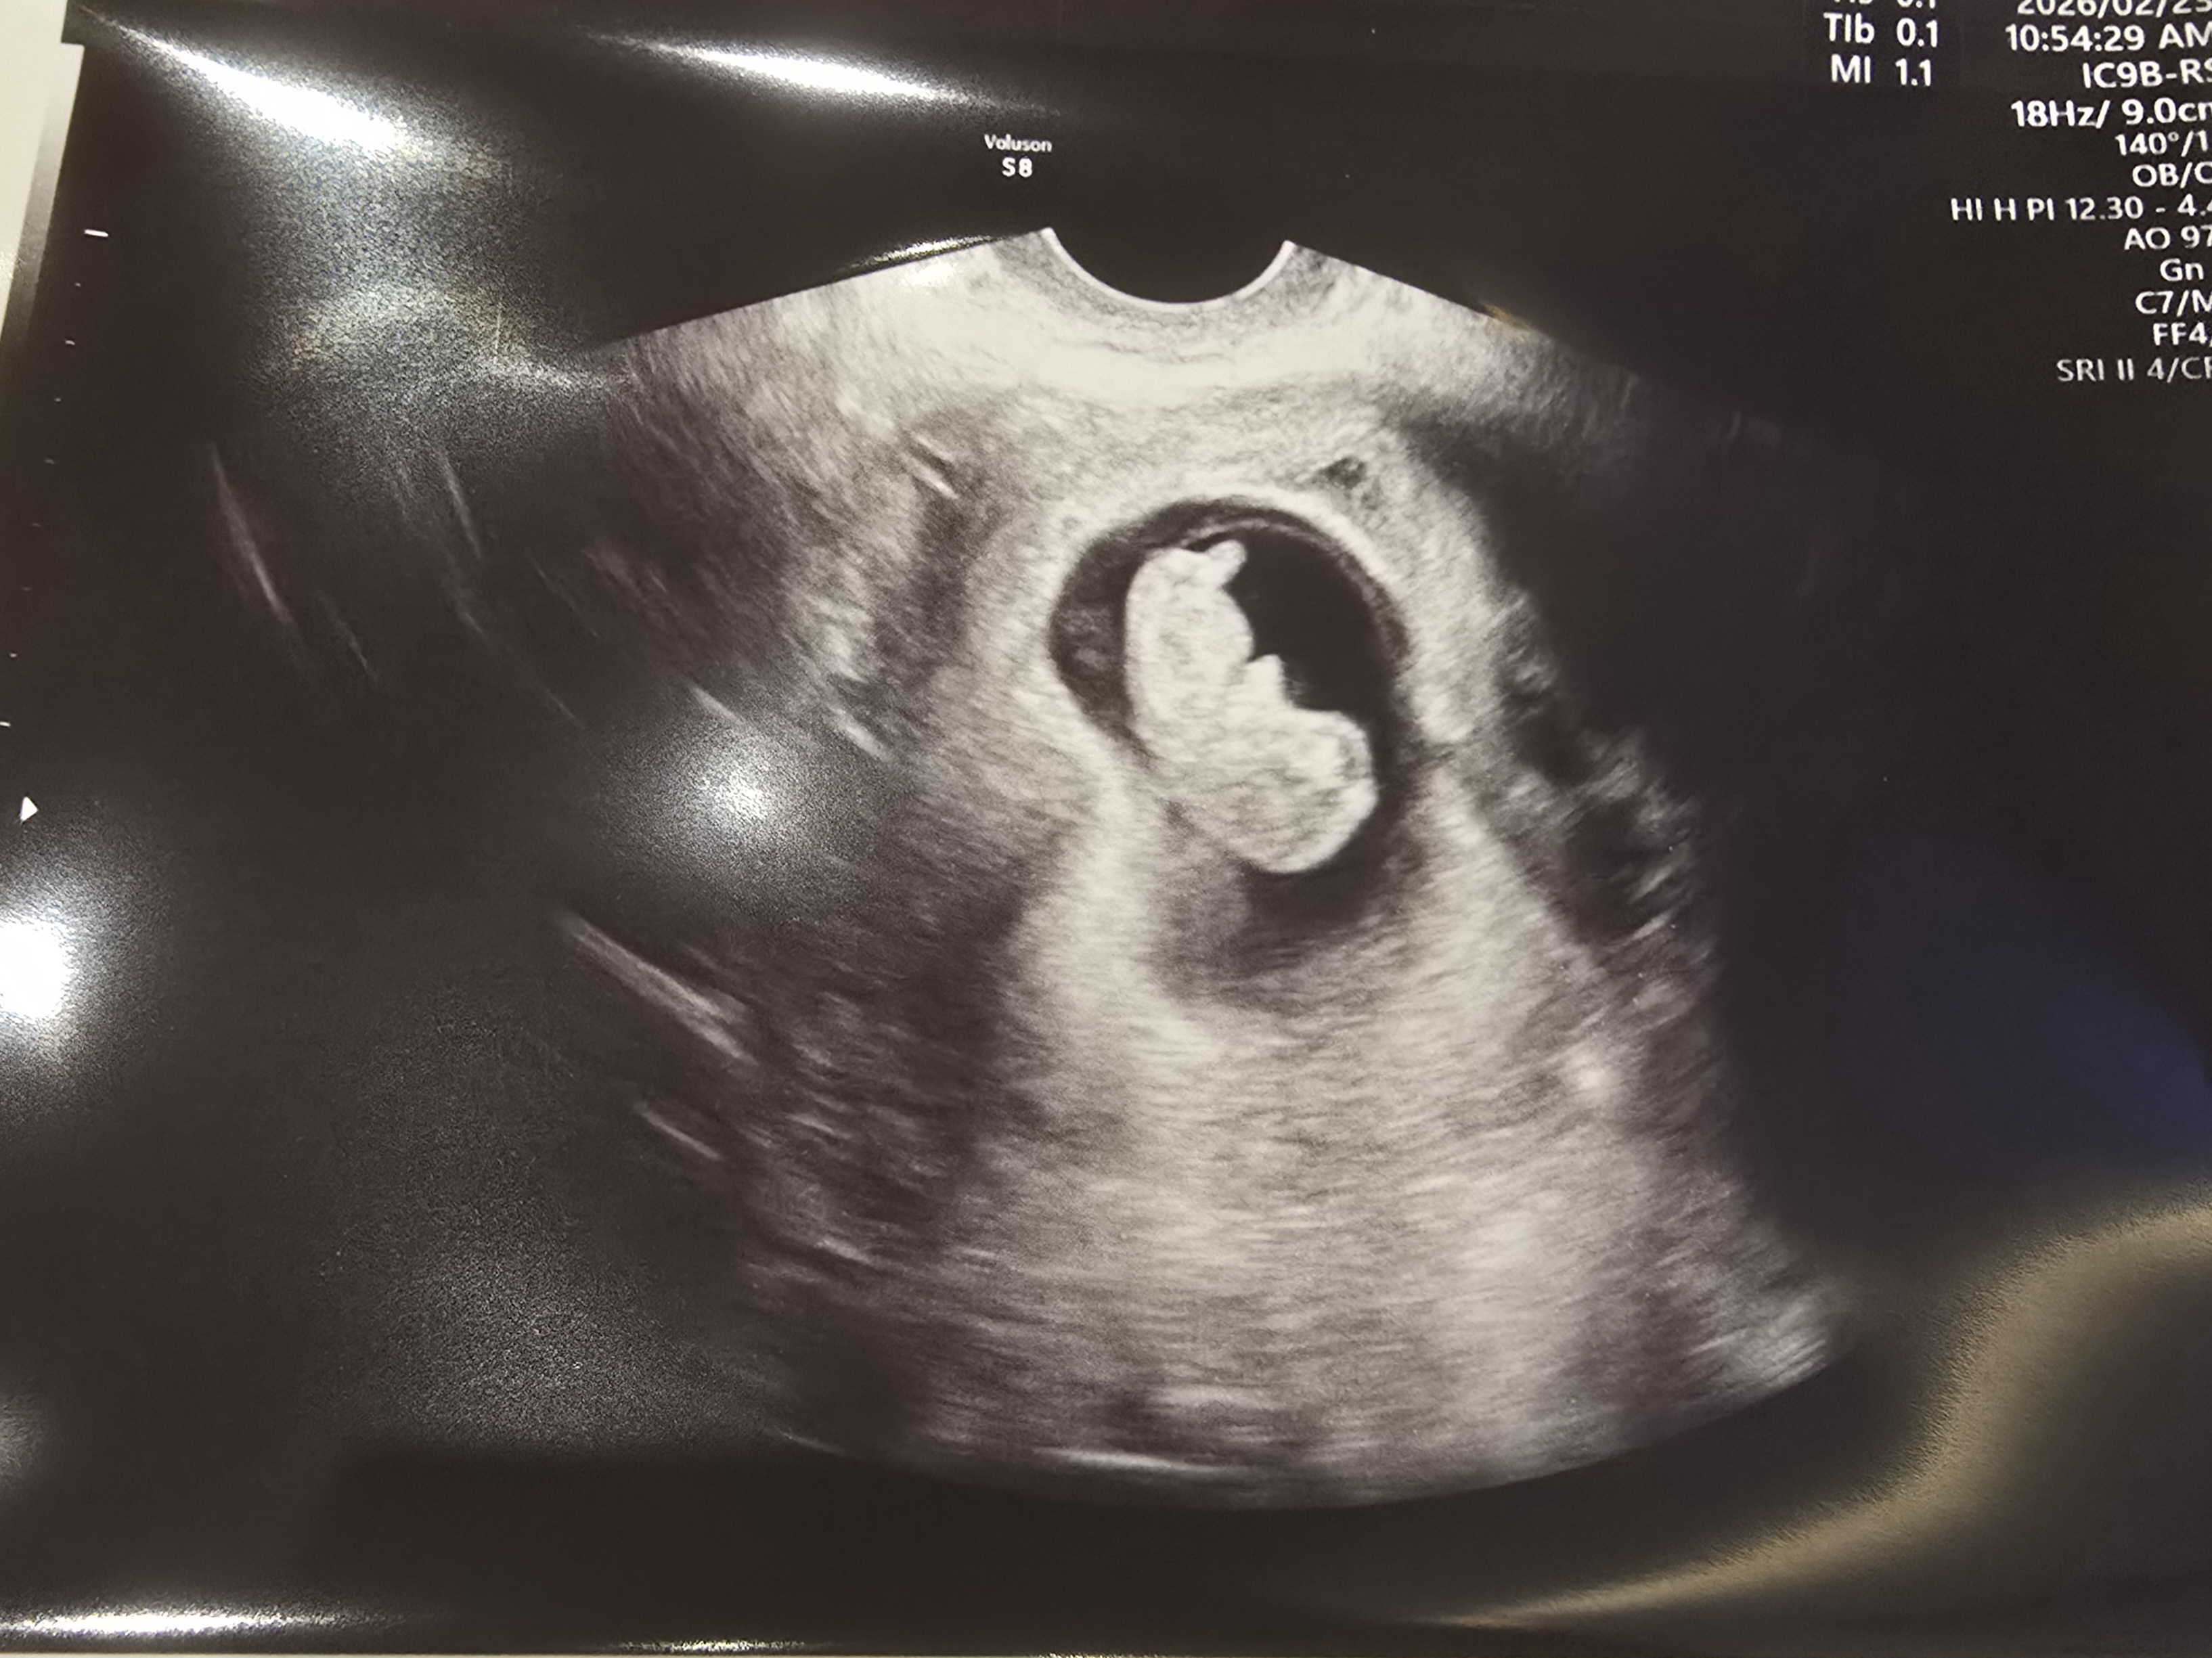

| 치료 도중 느꼈던 가장 기뻤던 순간과 절망적인 것들은 무엇인가요? 잊지 못할 경험이 있나요? | 가장 기뻤던 순간은 아기의 심장 소리를 처음 들었을 때입니다. 극초기에 출혈이 많아 매일 주사 치료와 약 복용으로 몸과 마음이 지쳐 있었지만, 심장 소리를 듣는 순간 그 모든 과정이 행복으로 바뀌는 듯한 마법이 생기더라구요^^ 반대로 가장 힘들었던 순간은 처음에는 쌍둥이 아기집을 확인했지만 출혈 이후 한 아이를 떠나보내고 하나의 아기집만 남아있다는 사실을 알게 되었을 때였습니다. 하지만 지금 남은 한 아이가 건강하게 자라고 있어 그 사실에 감사하며 다시 힘을 내고 있습니다. |